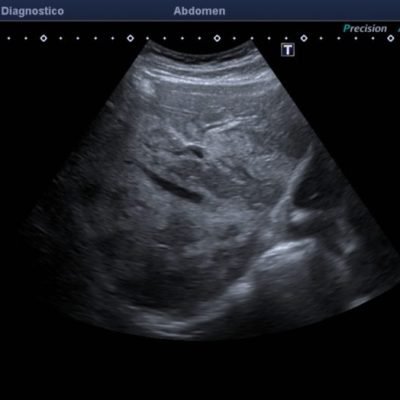

El médico de referencia le indica nueva ecografía de control, donde se observan múltiples y extensas lesiones focales hepáticas hiperecogénicas, redondeadas y confluentes, las cuales predominan en adyacencia a venas supra hepáticas, sin condicionar efecto de masa y sin alteración de la superficie hepática(fig. 1 y 2). Ante la valoración con Doppler color no presenta patrón de flujo peri ni intralesional y respeta el calibre de las venas supra hepáticas(fig. 3 y 4). Dada las características ecográficas se sospecha esteatosis focal multinodular confluente como principal diagnóstico presuntivo, siendo los diagnósticos diferenciales patologías de naturaleza infecciosa, tumoral o metastásica.